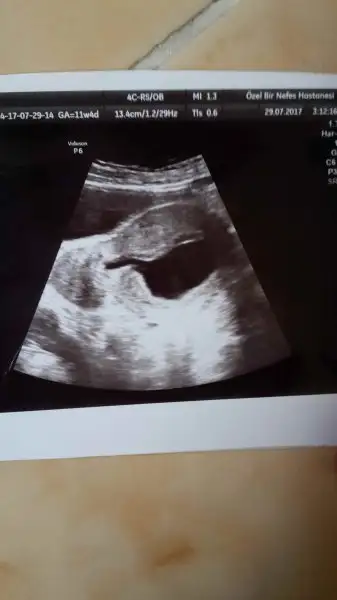

IMG-20170729-WA0019.webp

• IMG-20170729-WA0017.webp

IMG-20170729-WA0017.webp

10 KB · Görüntüleme: 89

• IMG-20170729-WA0015.webp

IMG-20170729-WA0015.webp

9,8 KB · Görüntüleme: 91